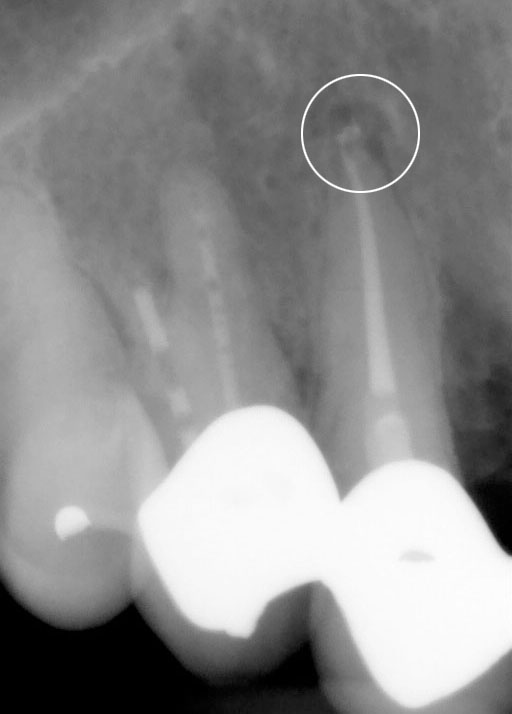

Op de tweede foto ziet u dezelfde kies net na de behandeling. Het kanaal is volledig schoon gemaakt en solide gevuld. Op de derde foto ziet u weer dezelfde kies een jaar na behandeling. De punt van de wortel laat geen zwarting meer zien en is volledig genezen.